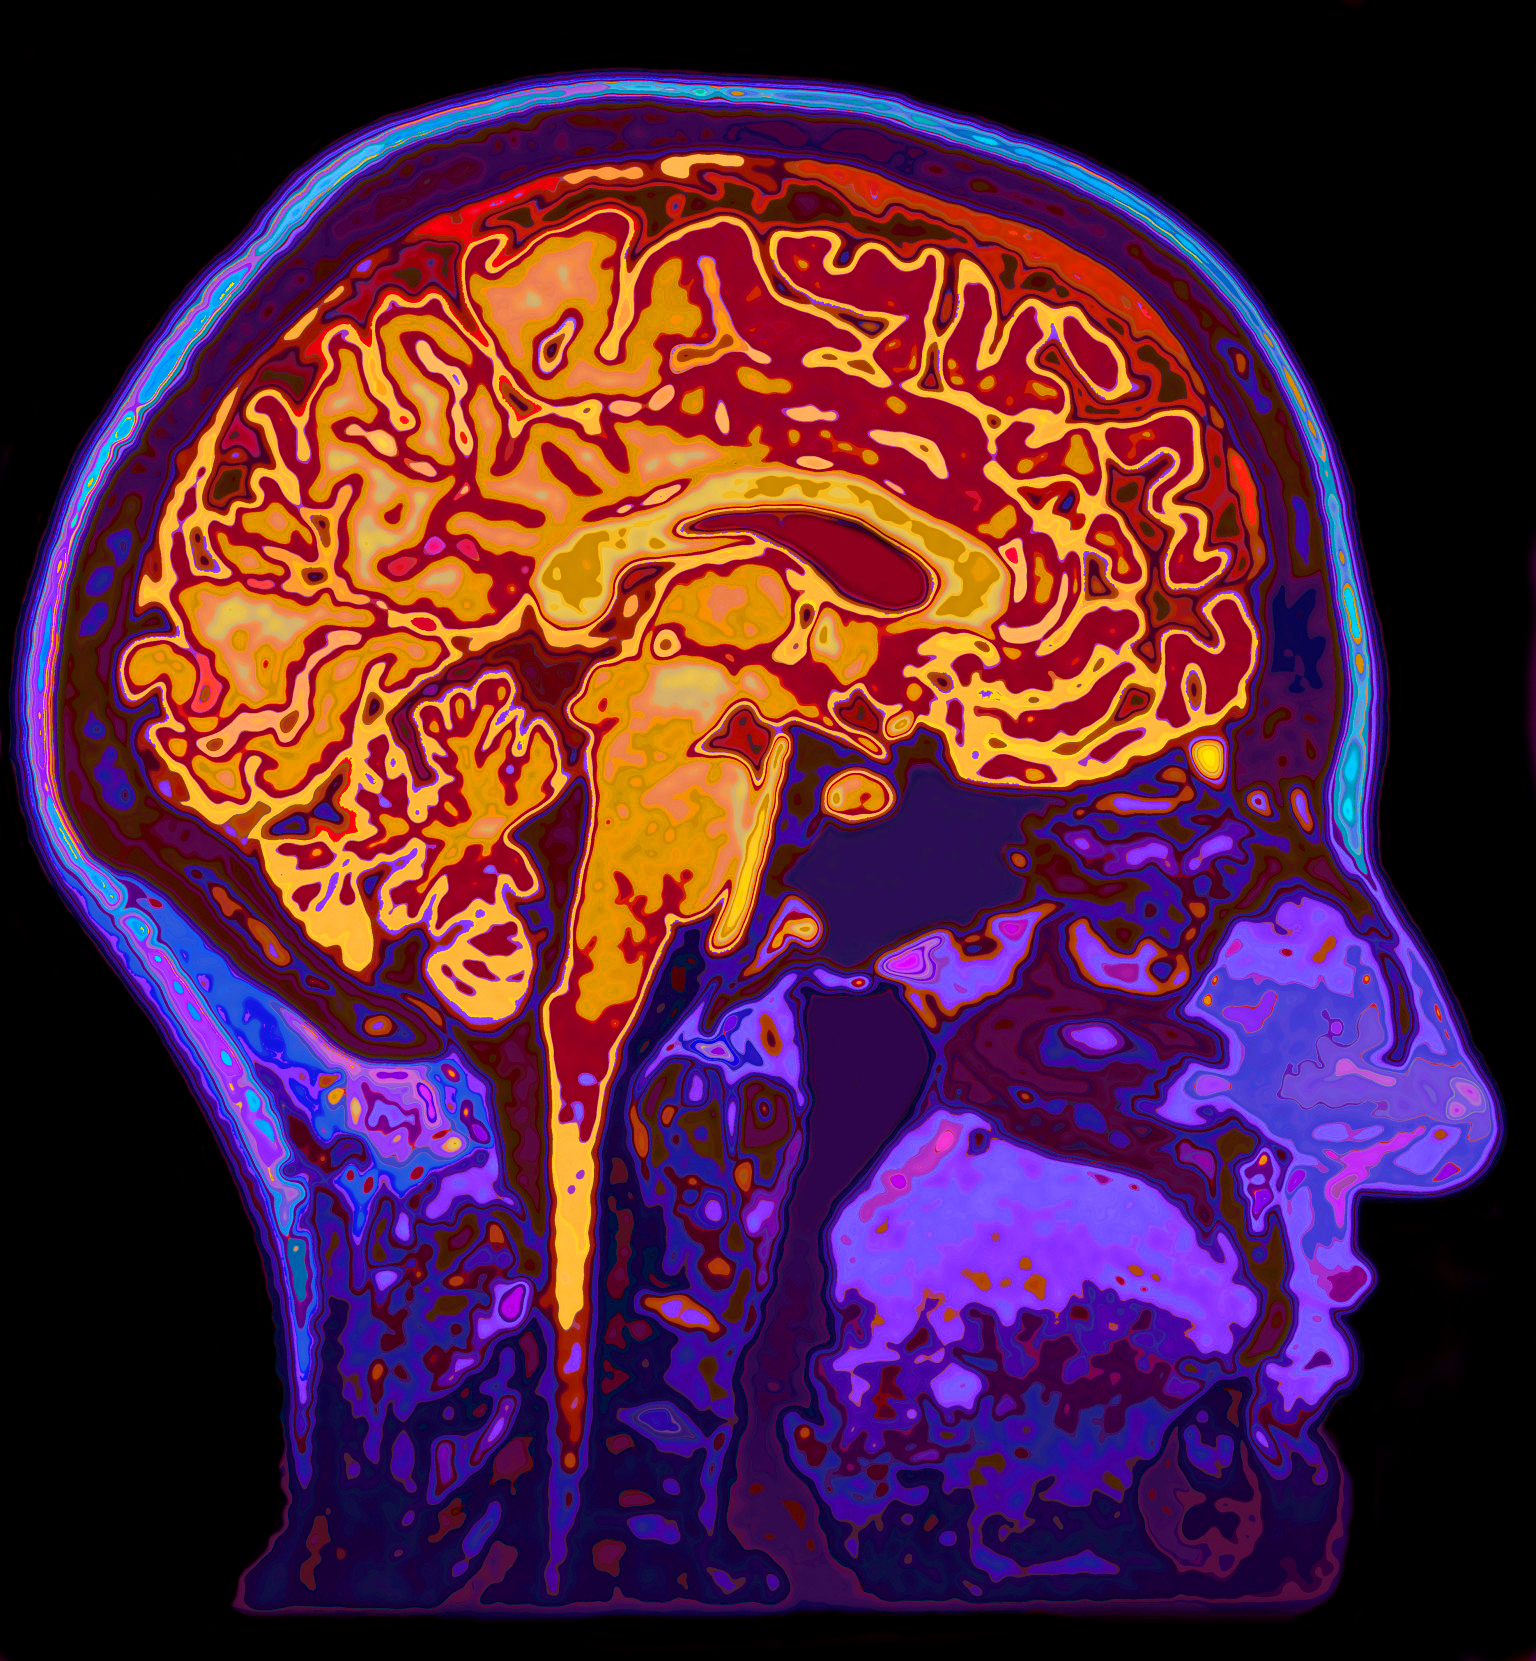

The most common form of brain cancer, Glioblastoma (GBM), is also the most deadly. The tumors grow rapidly and have steady access to a lot of blood. Surgery cuts out conspicuous tumors but not every cell can be located and removed, so full regrowth is the typical outcome. The other treatments available are chemotherapy and radiation. Yet, for those with GBM, half die after a year and only 10% survive three years.

Dr. Linda Liau and Dr. Robert Prins led the study at the university’s Jonsson Comprehensive Cancer Center and are pioneering immunology in combined treatment with chemotherapy to attack the tumors in mice. The decitabine weakens the tumors and prevents them from hiding from the body’s immune system. The new technique spurs the body to notice the ‘unmasked’ tumors so it can destroy those growths.